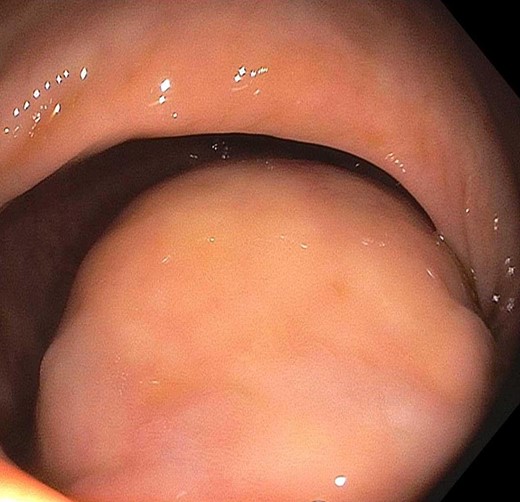

The patient is a 53-year-old male with past medical history significant for type II diabetes mellitus and hypercholesterolemia who underwent routine screening colonoscopy, during which a lobular mass of the proximal rectum was discovered (Fig. 1). The patient subsequently underwent an endoscopic ultrasound (EUS) with fine needle aspiration (FNA) biopsy (Fig. 2). Pathology displayed scant spindle cells with benign glandular epithelium suspicious for a spindle cell neoplasm. Accordingly, the patient was evaluated by a colorectal surgeon for further plan of care. A firm palpable lesion was appreciated on digital rectal exam. Various surgical approaches including laparoscopic low anterior resection as well as transanal excision were discussed with emphasis on complete excision due to the possibility of malignancy. The patient was taken to the operating room and an approximately 3 to 4 cm mass of the mid-rectum was appreciated; as the mass was found to be mobile, it was excised transanally by means of a stapler. Intra-operative pathological evaluation deemed the mass likely to be a low-grade spindle neoplasm, raising the possibility of a schwannoma or gastrointestinal stromal tumor (GIST). The procedure was well tolerated and the patient experienced full continence postoperatively.